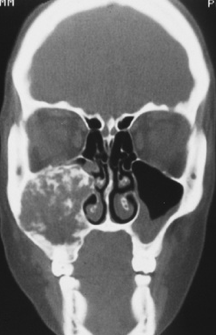

polyostotic fibrous dysplasia

gardner syndrome